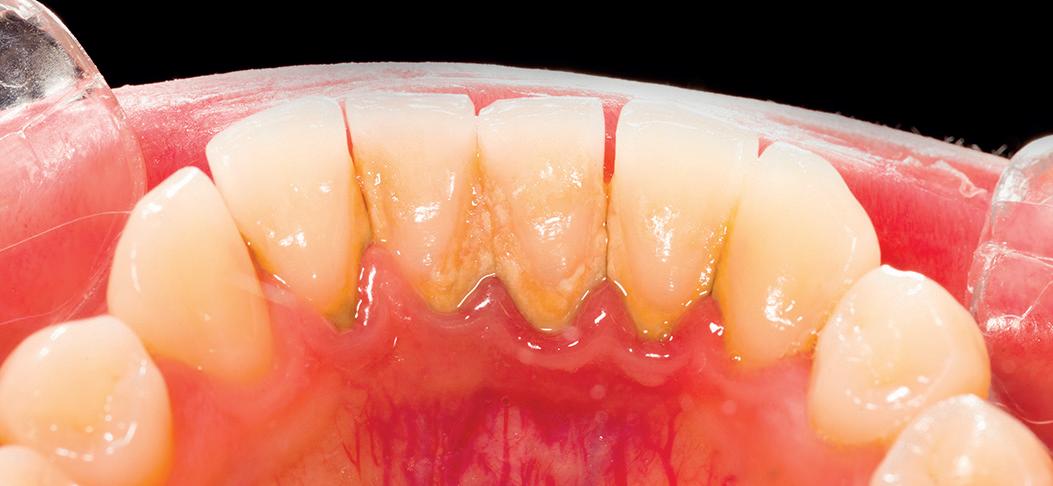

Before

After

Example of scaling.

Supragingival and subgingival ultrasonic scaling treatment with elliptical vibration track disperses the impact force between the tip and teeth.

The hardness of the titaniumalloy tip is lower thandental enamel which can reduce damage to teeth.